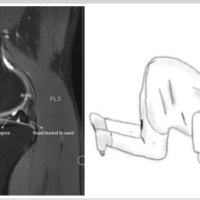

The patient was an immunocompetent 41-year-old female who presented to our clinic with a painful and unstable right knee prosthesis, with the index procedure performed approximately 5 years prior at an outside institution. The patient was a poor historian, and the indication for the index procedure was not clear, and operative reports were not available for review. Clinical examination revealed a right knee with varus deformity, coronal plane instability, and a moderate joint effusion. Imaging demonstrated femoral component loosening with osteolysis of the lateral distal femoral condyle (Fig. 1). An infectious workup was initiated, and inflammatory markers were within normal limits, with a C-reactive protein of 3 mg/L and erythrocyte sedimentation rate of 8 mm/h. As surgical intervention was planned to address a loose femoral implant, a joint aspiration was performed. Initial right knee arthrocentesis revealed a synovial white blood cell count (WBC) of 1,870 cells per µL, 60% polymorphonuclear (PMN) cells, and negative aerobic and anaerobic cultures. Evaluation of the sample for acid-fast bacilli (AFB) was not performed. The patient was directed toward anticipated surgical intervention – revision TKA versus antibiotic spacer. Surgical scheduling was prolonged for several reasons: (1) poor patient follow-through with obtaining an magnetic resonance imaging to evaluate the integrity of the medial collateral ligament; (2) the patient took a significant period of time to achieve any reduction in smoking; and (3) difficulty obtaining primary care clearance. Due to this prolonged period before scheduling and persistent clinical concern for PJI, a repeat arthrocentesis was performed. This aspiration yielded a synovial WBC count of 1,822 cells/µL and 37% PMNs, yet cultures were positive for Mycobacterium intracellulare after 17 days. Given the low PMNs yet positive mycobacterial culture in an otherwise immunocompetent host, this result was initially considered a potential false positive due to suspected sample contamination. To confirm or refute this discrepancy, a repeat arthrocentesis was performed before surgery. The final pre-operative sample demonstrated a WBC of 2,397 cells/µL with 79% PMNs, negative aerobic and anaerobic cultures, and again positive AFB culture for Mycobacterium intracellulare. A diagnosis of PJI was made, and a two-stage exchange consisting of femoral and tibial component removal with interval placement of an articulating antibiotic spacer was planned (Fig. 2).